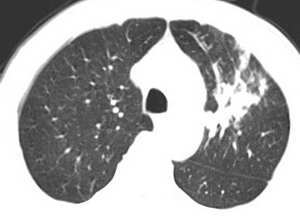

男,58岁,咳嗽1月加重1周,伴痰中带血

左肺上叶胸膜下不规则团块阴影,内见空泡,边缘光整,肺纵比率>50%,支持左肺癌的诊断。

左上肺病灶与胸膜脂肪线存在,未见明显胸膜凹陷征,虽然病灶边缘不规则,但未见明显“短毛剌、切迹征、免耳征、血管束集征”,其间亦见条索状、斑点状影,认为左上肺结核或炎性病变>周围型肺癌。

病灶比较虚 周围有明显渗出 卫星灶及条素影 病灶边缘有棘突 胸膜外脂肪层存在考虑结核

考虑肺结核可能性大。理由1.病灶形态不规则,其周有卫星灶,2.病灶没有毛刺征,灶周出现粗大索条影.